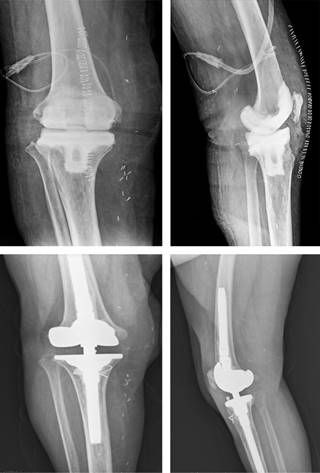

Los defectos óseos evidenciados, clasificados según AORI, se dividen en función de su región. En la tibia, la mayoría, 25 (69.4%) pacientes, no presentaban defecto óseo. De los 11 casos restantes, siete (19.4%) presentaban un defecto tipo 1; tres (8.3%) defecto tipo 2A (Figura 2); y uno (2.8%) defecto tipo 2B.

Figura 2: Radiografías anteroposterior (izquierda) y lateral (derecha). Paciente con infección crónica protésica tras primer y segundo tiempo quirúrgico. Defecto AORI tibial tipo 2A y femoral tipo 3.

En relación a los defectos femorales, 12 pacientes (33.3%) presentaron defectos tipo 1; 10 (27.8%) tuvieron defectos tipo 2A, siendo el mismo número (27.8%) para los defectos tipo 2B. Por último, dos (5.6%) casos tuvieron defectos severos tipo 3. Solo en dos (5.6%) no se evidenciaron defectos femorales.